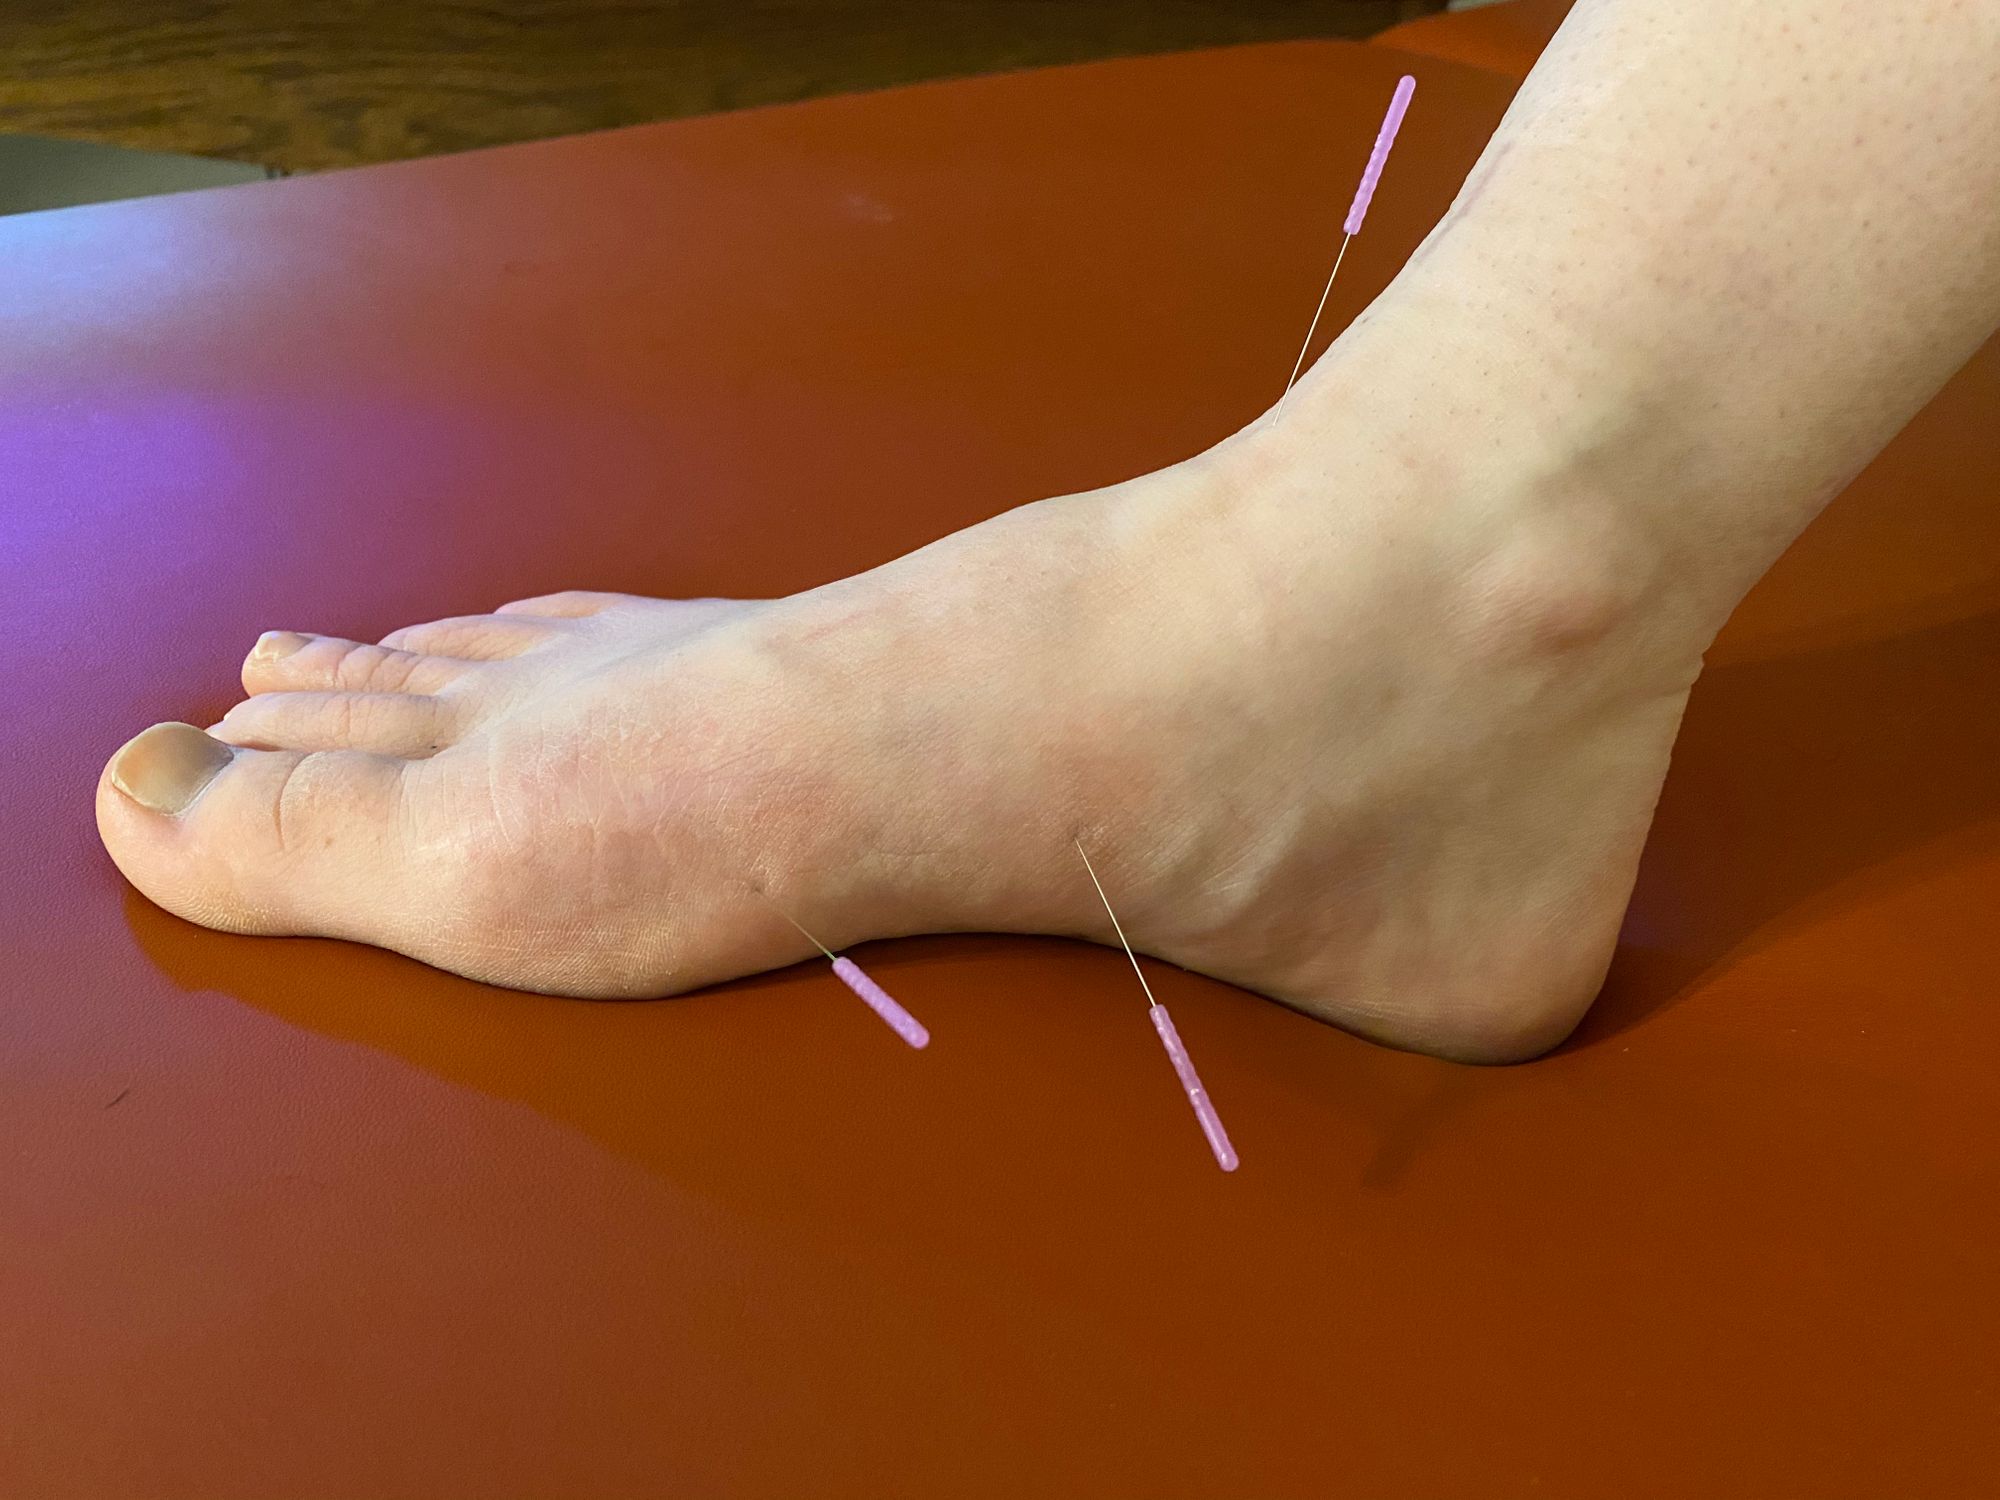

Dry needling calf plantar fasciitis outlet

Dry needling calf plantar fasciitis outlet, Dry Needling Therapy as a Potential Treatment Option for Plantar Fasciitis Podiatry Today outlet

Dry needling calf plantar fasciitis outlet

Dry Needling Therapy as a Potential Treatment Option for Plantar Fasciitis Podiatry Today

What is Dry Needling and can it help me with my heel pain

Dry Needling Manipulation to Treat Cure Plantar Fasciitis Foot Pain Intricate Art Spine Body Solutions

Therafit Physical Therapy Dry Needling in Lowell MA

Best Treatments for Plantar Fasciitis Back in the Game PT

Trigger Point Dry Needling the Calf